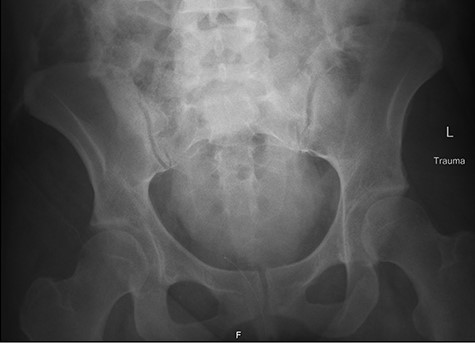

Fetal HR was measured at 135 bpm. Chest X-ray revealed a small apical pneumothorax and a fractured right clavicle. She was taken to the computed tomography (CT) scanner where CT-CAP with contrast revealed a Grade 2 liver laceration, Grade 3 splenic laceration and bilateral Grade 4 kidney injuries with extravasation of contrast on the renal delay, suggestive of urine extravasation. No pelvic fracture was found on imaging (Figs 1 and 2).